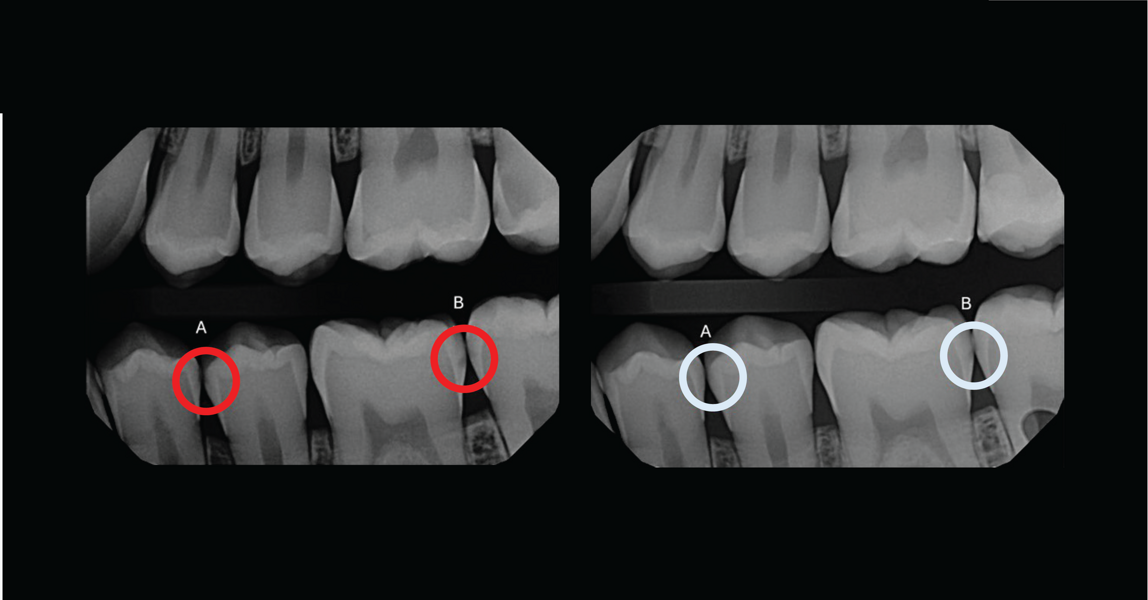

Dr. Haley Abivardi: Curodont Repair Fluoride Plus addresses a common issue that affects 80% of patients in the dental chair: early caries, often found on interproximal sites or as white spots after orthodontic treatment. As dental professionals, we refer to these as “watch areas” because, until now, there has been no effective solution. Leaving patients untreated can lead to caries progression and an increased risk of severe secondary disease.

Dr. Haley Abivardi: It is very encouraging to see the before-and-after cases shared by dental professionals and to have the support of the academic world, including ongoing collaborations with leading dental schools. This solution supports dental professionals in transforming their approach by addressing the subclinical signs of caries with a nonsurgical medical treatment.

Curodont offers a noninvasive and easy-to-apply solution that enhances patient care and outcomes. More than 200,000 teeth have been treated with this product in the U.S. over the past two years, enabling early intervention for watch areas that were previously left untreated.